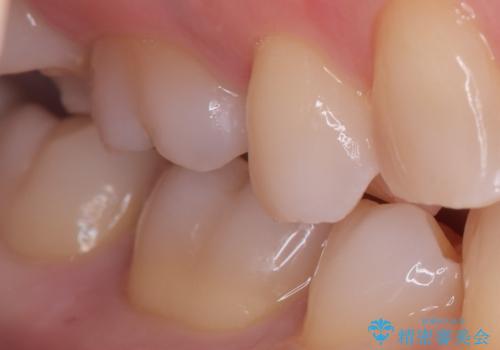

銀歯を丁寧に取り除き、形態を整えた上で、セラミックインレーで修復しました。

当院のセラミックインレーはe-max プレスインレーで製作しています。